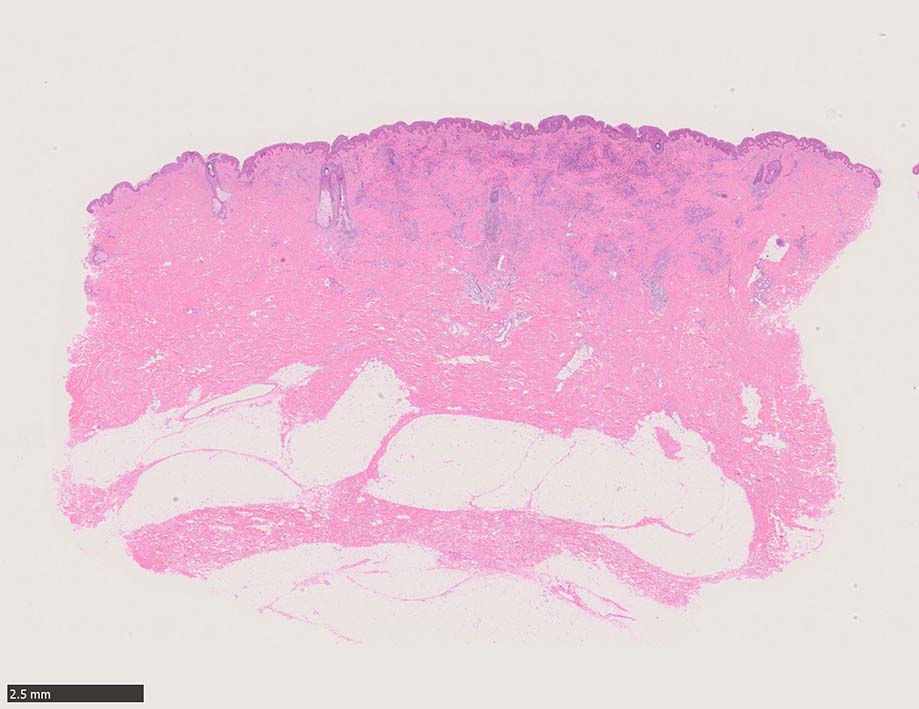

局面状病変の病理

病変は真皮から皮下脂肪織に及ぶようになり, 血管内皮様細胞による新生管腔の増加と拡張, 浮腫が著明になる. 赤血球漏出やヘモジデリン貪食細胞もめだつようになる.

膠原線維間に紡錘形細胞が増生してくる.

参考症例:中部交見会1246: Kaposi's sarcoma 右足内側部皮膚/ 40歳代男性 焼津市立病院 久力 権先生